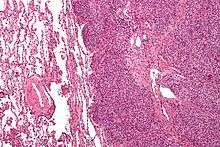

| Micrograph of metastatic Ewing sarcoma (right of image) in normal lung (left of image). PAS stain. | |

Ewing's sarcoma is a small-blue-round-cell tumor that typically has a clear cytoplasm on H&E staining, due to glycogen. The presence of the glycogen can be demonstrated with positive PAS staining and negative PAS diastase staining. The characteristic immunostain is CD99, which diffusely marks the cell membrane. Morphologic and immunohistochemical findings are corroborated with an associated chromosomal translocation, of which several occur. The most common translocation, present in about 90% of Ewing sarcoma cases, is t(11;22)(q24;q12),[12][13] which generates an aberrant transcription factor through fusion of the EWSR1 gene with the FLI1 gene.[14]